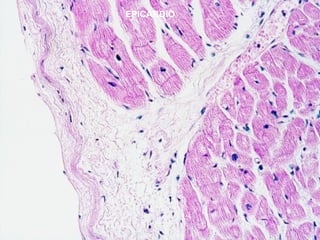

Pared cardiaca (3 capas)

-Epicardio : - capa fibrosa interna de tejido conectivo

- capa serosa externa o mesotelio ( capa

visceral del pericardio).

-Miocardio: formado por varias capas de células musculares estriadas

cardíacas de diferente orientación.

-Endocardio: formado por un endotelio y un subendotelio que es una

fina capa de tejido conectivo laxo.

EPICARDIO